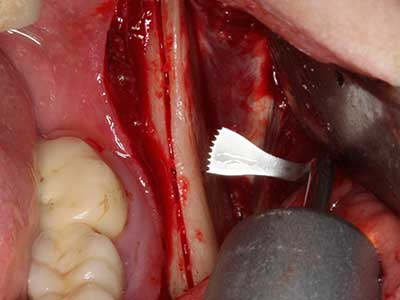

Indication: Autologous bone harvesting

Autologous bone transplants are used in the form of blocks, shells, rings and are also combined with bone replacement materials as chips. If the implant site is prepared at the same time as the augmentation, various bone filter systems have proven effective for collecting the resulting bone chips. As an alternative, the implant site can be prepared using a low-speed device without irrigation. If an implant is not inserted, bone chips can be harvested from the periphery with bone scrapers. This is also possible with piezo surgery using specialized attachments that yield higher-quality bone chips compared chips harvested with round drills, as has been confirmed in a study comparing the two methods (Chiriac, Herten et al. 2005).

Piezo surgery has additional advantages when harvesting bone blocks. In addition to the high precision with osteotomy described above, the use of the thin saw tips specifically minimizes loss of material. Greater loss of material during harvesting can be expected with the thicker instrument tips, particularly when using Lindemann drills (Lakshmiganthan, Gokulanathan et al. 2012). The basal separation, which is necessary particularly for retromolar block transplants, is simplified by specially designed rectangular saws, with the result that piezo surgery is viewed as a precise, simple and safe procedure for harvesting retromolar bone blocks (Happe 2007) (Fig. 1-12).